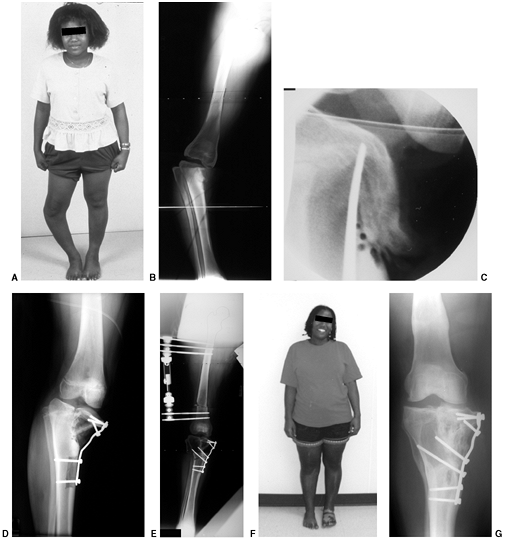

![]() |

Figure 28.15 A:

These anteroposterior radiographs show focal changes of unilateral stage IV Blount disease. The medial tibial physis is indistinct. These changes are suggestive of physeal bar formation. B: A computed tomography (CT) scan shows the deformity in the medial physis. The growth plate has a vertical rather than horizontal orientation. A bridge of bone is clearly evident here. Varus will rapidly recur following osteotomy if the physeal bar is not recognized and treated. C: These postoperative films show correction of the varus and resection of the bar. The defect created by excision is filled with radiolucent methylmethacrylate (Cranioplast). D: Subsequent films show recurrent bar formation with gradual loss of correction over 2 years. E: A second excision of the physeal bar along with lateral physeal stapling has resulted in improved alignment. F: Following removal of the staples, varus has gradually recurred. The abnormal medial physis tends to close prematurely. |

Continued normal growth in the medial physis generally does not equal

premature medial physeal closure. A second bar resection and varus

recurrent bars in younger patients (Fig. 28.15D).

If lateral hemiepiphyseal stapling has been done, the patient requires

surgery is indicated. Left untreated, progression of bar formation will

Physeal bar resection in conjunction with a varus-correcting osteotomy

are then performed (Fig. 28.15C).